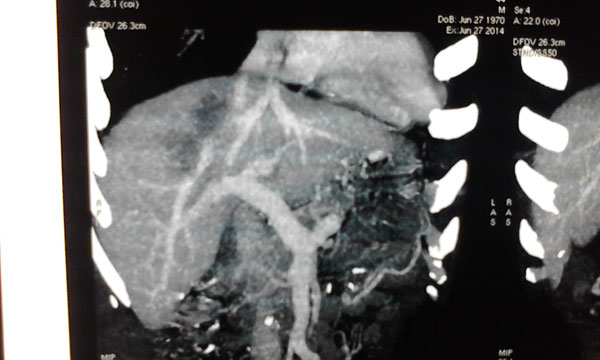

患者确诊为原发性肝癌,肿瘤位于肝脏的ⅦⅧ段,侵犯肝右静脉,与肝中静脉关系密切,必须行右半肝全切除,残留肝体积需达到标准肝体积的40%左右才能保证术后肝功能正常,而患者的残留肝脏体积仅占标准肝体积的30%,传统上认为达不到手术切除的要求。韦杨年主任决定采用世界肝脏外科革命性的二步肝切除技术。

7月4日卫生部肝胆肠中心的李年丰教授和我院肝胆外科主任韦杨年副教授及其团队,为患者实施采用第1 步腹腔镜下肝脏离断和门静脉右支结扎,以此减少右侧肝的血液供应,同时将左、右半肝劈开分离。

肿瘤与肝动脉

肿瘤与肝静脉